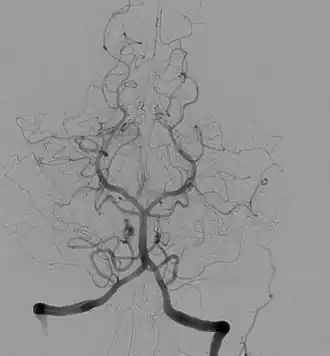

Ангиогра́фия (греч. ἀγγεῖον — сосуд + γράφειν — писать) — класс методов контрастного исследования кровеносных сосудов, используемый в рамках рентгенографических, рентгеноскопических исследований, в компьютерной томографии, магнитно-резонансной томографии, применяемый в гибридной операционной.

Ангиография показывает функциональное состояние сосудов, окольного кровотока и протяжённость патологического процесса. Исследование позволяет выявить повреждения и пороки развития кровеносных сосудов: аневризмы, сужения сосудов, мальформацию, нарушения проходимости сосудов (атеросклероз, тромбоз), а также повреждения и пороки развития различных органов, опухоли. Например, ангиограмма сосудов головного мозга со специфической картиной помогает диагностировать болезнь моямоя.